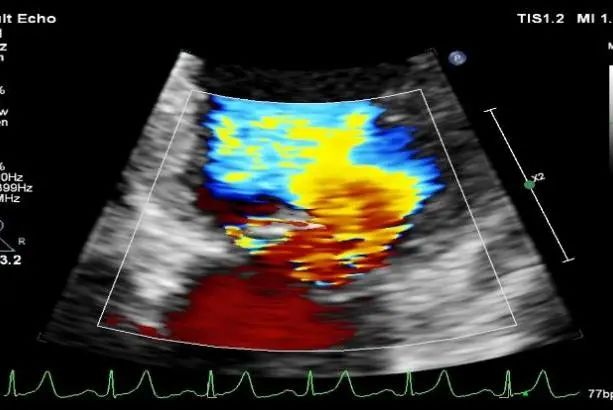

TEE短轴脱垂区域显示(P2、P3区大范围脱垂)

TEE短轴脱垂区域显示(color,血流来源于P2、P3区)

肺静脉收缩期反向血流